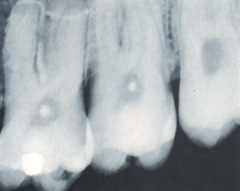

internal resorbsion

Front

circle inside the pulp chamber

Back